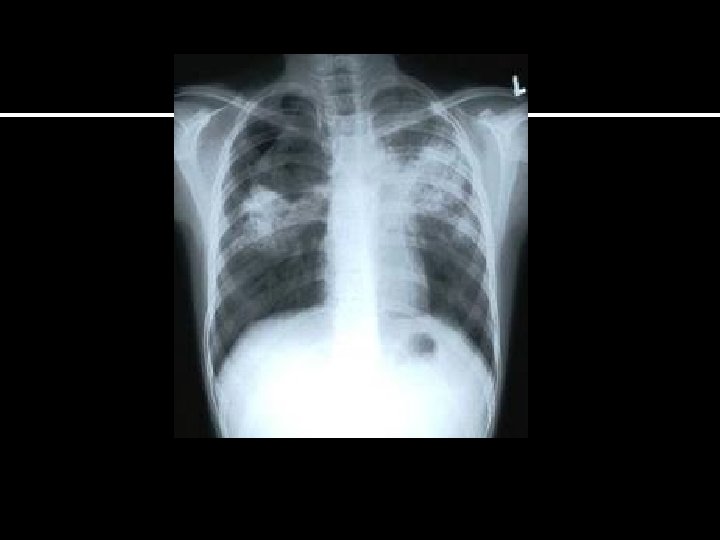

1. PUL TUBERCULOSIS • SAMPLE COLLECTION • MICROSCOPY • CONCENTRATION METHODS • CULTURE • SENSITIVITY TESTS • ANIMAL INOCULATION • NUCLEIC ACID TECHNOLOGY • IMMUNODIAGNOSIS